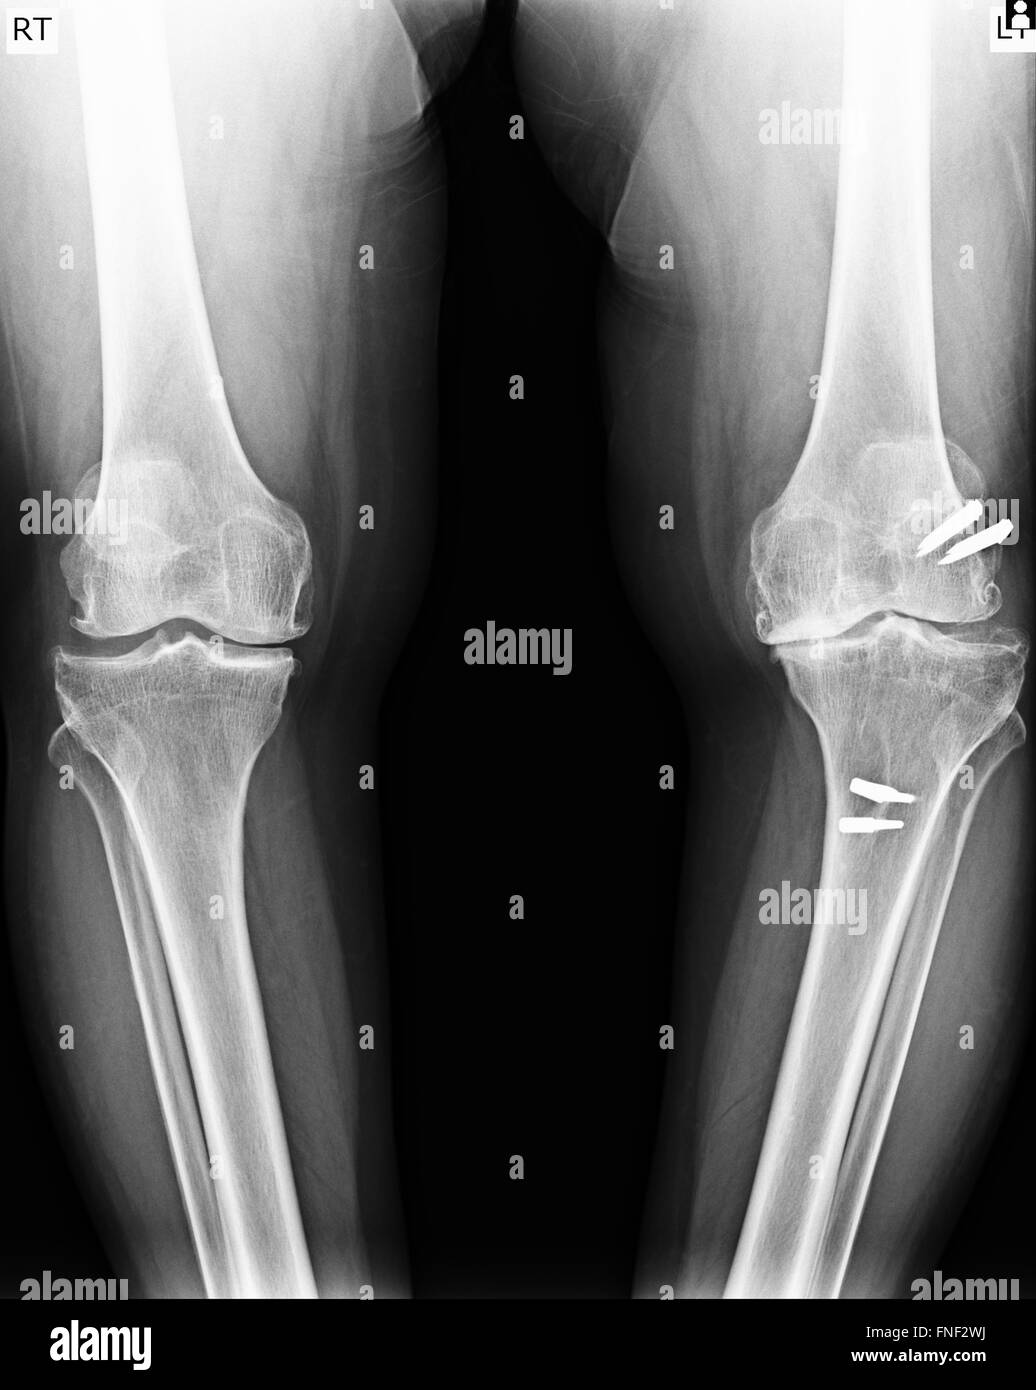

From www.alamy.com

Total knee replacement x ray image hires stock photography and images Knee Replacement Xr The surgeon makes a cut down the front of your knee and moves your kneecap to the side so. The most common reason for. Find out what a knee replacement involves, when it might be recommended, and how it can help with knee pain and movement. Total knee arthroplasty (tka) is the most commonly performed joint replacement surgery in the. Knee Replacement Xr.